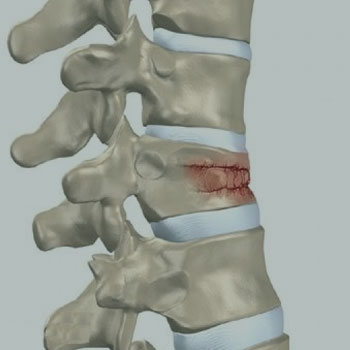

HÉRNIA DISCAL

DOENÇA DEGENERATIVA DISCAL